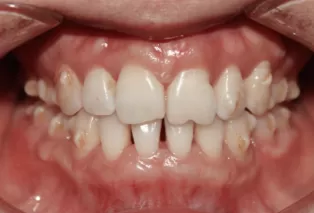

Intraoral photos